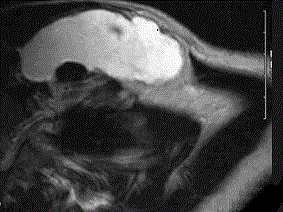

问题 37岁女性,左侧颈部肿块渐进性增大,无压痛,局部皮温不高,CT、MRI扫描如图所示,请选择正确的描述或诊断 ( )

选项 A、MRI的TWI呈高信号,其内可见分隔 B、考虑为淋巴管囊肿 C、增强扫描未见强化 D、MRI的TWI呈低信号 E、CT发现左侧颈后三角区可见低密度肿块影

答案 ABCDE